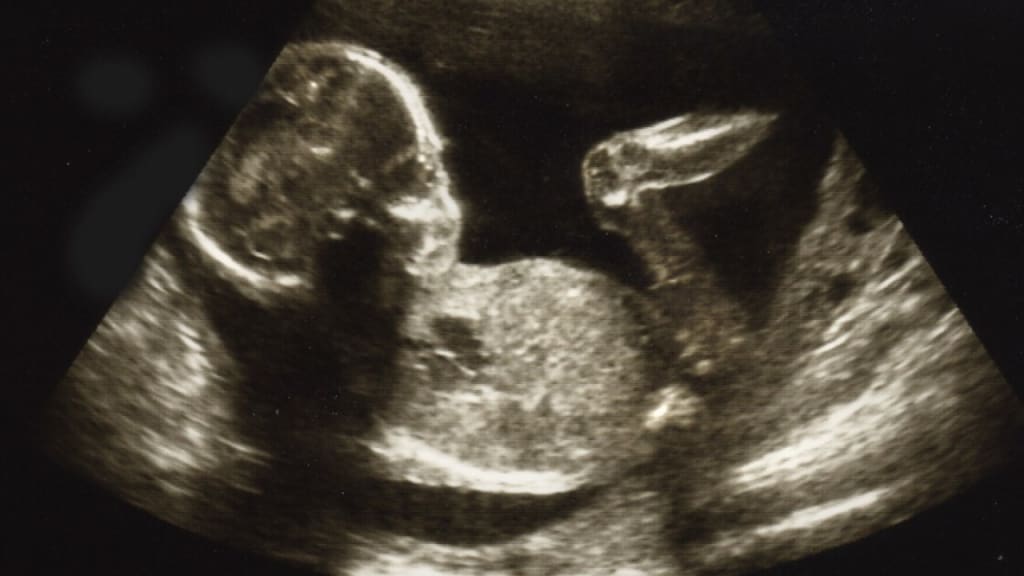

With my first pregnancy I had a trans-vaginal ultrasound at 7 weeks gestation and he was a tiny little dot, my husband and I were sure it was a boy and we intended to name him Alexander. My breasts were unbelievably sore and my stomach was really bloated so whilst only 7 weeks along I looked about 3 months, and I loved it. After years of trying, we had finally done it and we were both on cloud nine. Immediately upon hearing the magical words “It’s positive” I took to rubbing my tummy dreamily.